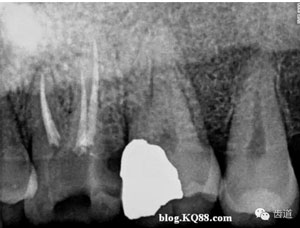

將加熱器溫度調到200℃,輕按手柄上的開關,將確定好操作長度的攜熱頭插入根管內,加熱3-4秒鐘左右,停止加熱保持8-10秒鐘左右。

再加熱1秒鐘,停止加熱后迅速帶出距工作長度5mm以上的多余牙膠尖。后用選擇好的垂直加壓器加壓。完成根尖1/3的充填。

開啟熱牙膠注壓充填器,將手柄頭插入根管內,將尖端頂在充好的根尖 1/3牙膠處,輕按開關,牙膠即可流出。充2-3MM后換合適的垂直加壓器加壓。

重復上一步驟直到完成根管冠方2/3的充填。